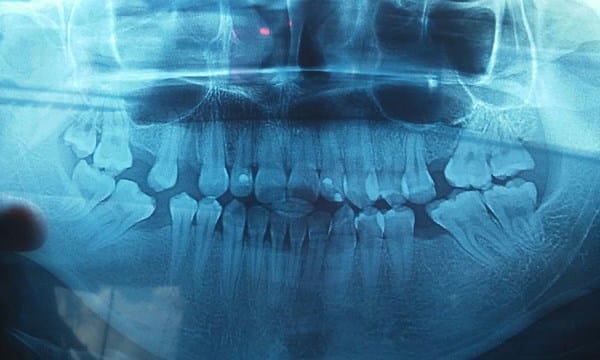

Tengo 22 años y me faltan 4 muelas y un premolar, todas estas extracciones me las a realizado la misma dentista, la cual nunca me comentó que podía hacerme una endodoncia en mis piezas perdidas y ahora quiere realizar me un puente a pesar de mi edad y yo no quiero por miedo a que tallen mis otros dientes, ahora me iba a realizar un implante en el esprecio del premolar, pero esta "dentista" me dejó un pedazo de raíz y me tengo que esperar otros dos meses en lo que se recupera mi encia, está situación me a deprimido mucho sobre todo por el miedo a quedarme sin ningún diente. Ya eh visitado otros tres dentistas uno me recomienda realizar un puente Maryland y otro un tratamiento con brackets, el último el implante y tratar la infección .

Mi pregunta es cual sería el tratamiento que más me beneficiaría y si me realizó el implante dental después que termina su vida útil, tendría que ponerme todo o ya no se podría realizar, nada y se tendría que poner un puente